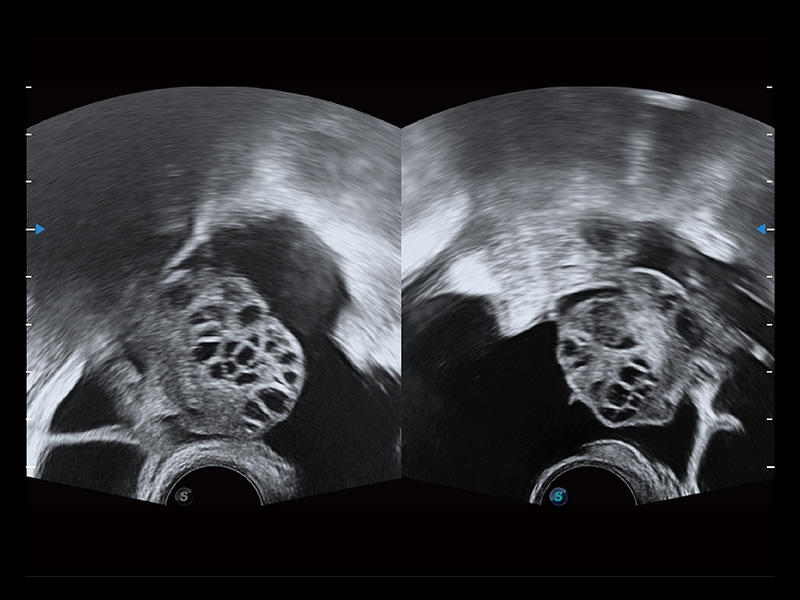

“生育问题”即关系民族复兴,也关系亿万家庭的幸福。随着婚育年龄推迟、社会压力增加等因素,越来越多人群也面临着“生不出、生不好”的问题。辅助生殖作为治疗不孕不育最有效的方法之一,也逐渐成为育儿新希望。而超声检查能为生殖需求人群的初诊评估提供宝贵的信息。 P20 Elite是狗万官方网站匠心打造的一款生殖应用型彩超。她继承狗万官方网站高端极光平台,突破性地将多款新型芯片及硬件模块进行整合,均衡了高端系统性能与小巧灵动机身。P20 Elite卓越的图像质量搭载专科探头,旨在为您提供全面的辅助生殖解决方案。

P20 Elite配备了丰富的生殖探头群和临床应用功能,在卵泡监测、穿刺取卵、胚胎移植、妊娠确认等领域,为生殖需求人群提供了新的临床机会,重新定义高端超声如何应用于生殖健康检查。